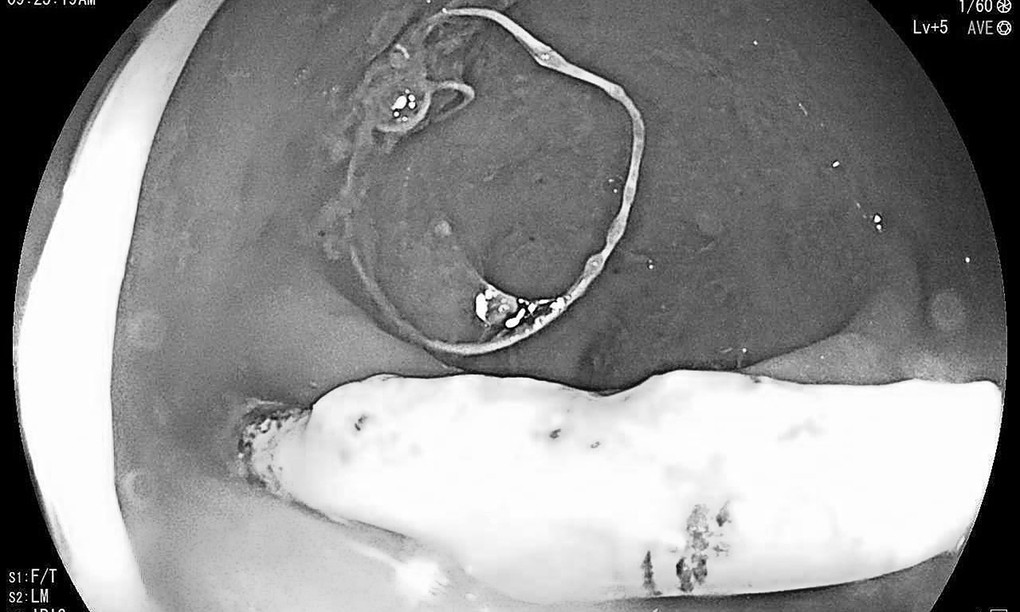

Bệnh nhân khám tại Bệnh viện Hữu nghị Việt Nam - Cu Ba Đồng Hới, sáng 7/7. Khi nội soi đại tràng, các bác sĩ phát hiện một vòng tránh thai nằm lạc chỗ, đâm xuyên thành trực tràng. Một nửa chiếc vòng nằm trong ổ bụng, nửa còn lại nằm trong lòng trực tràng.

Bác sĩ chỉ định bệnh nhân nhập viện để phẫu thuật lấy chiếc vòng tránh thai ra khỏi thành trực tràng.